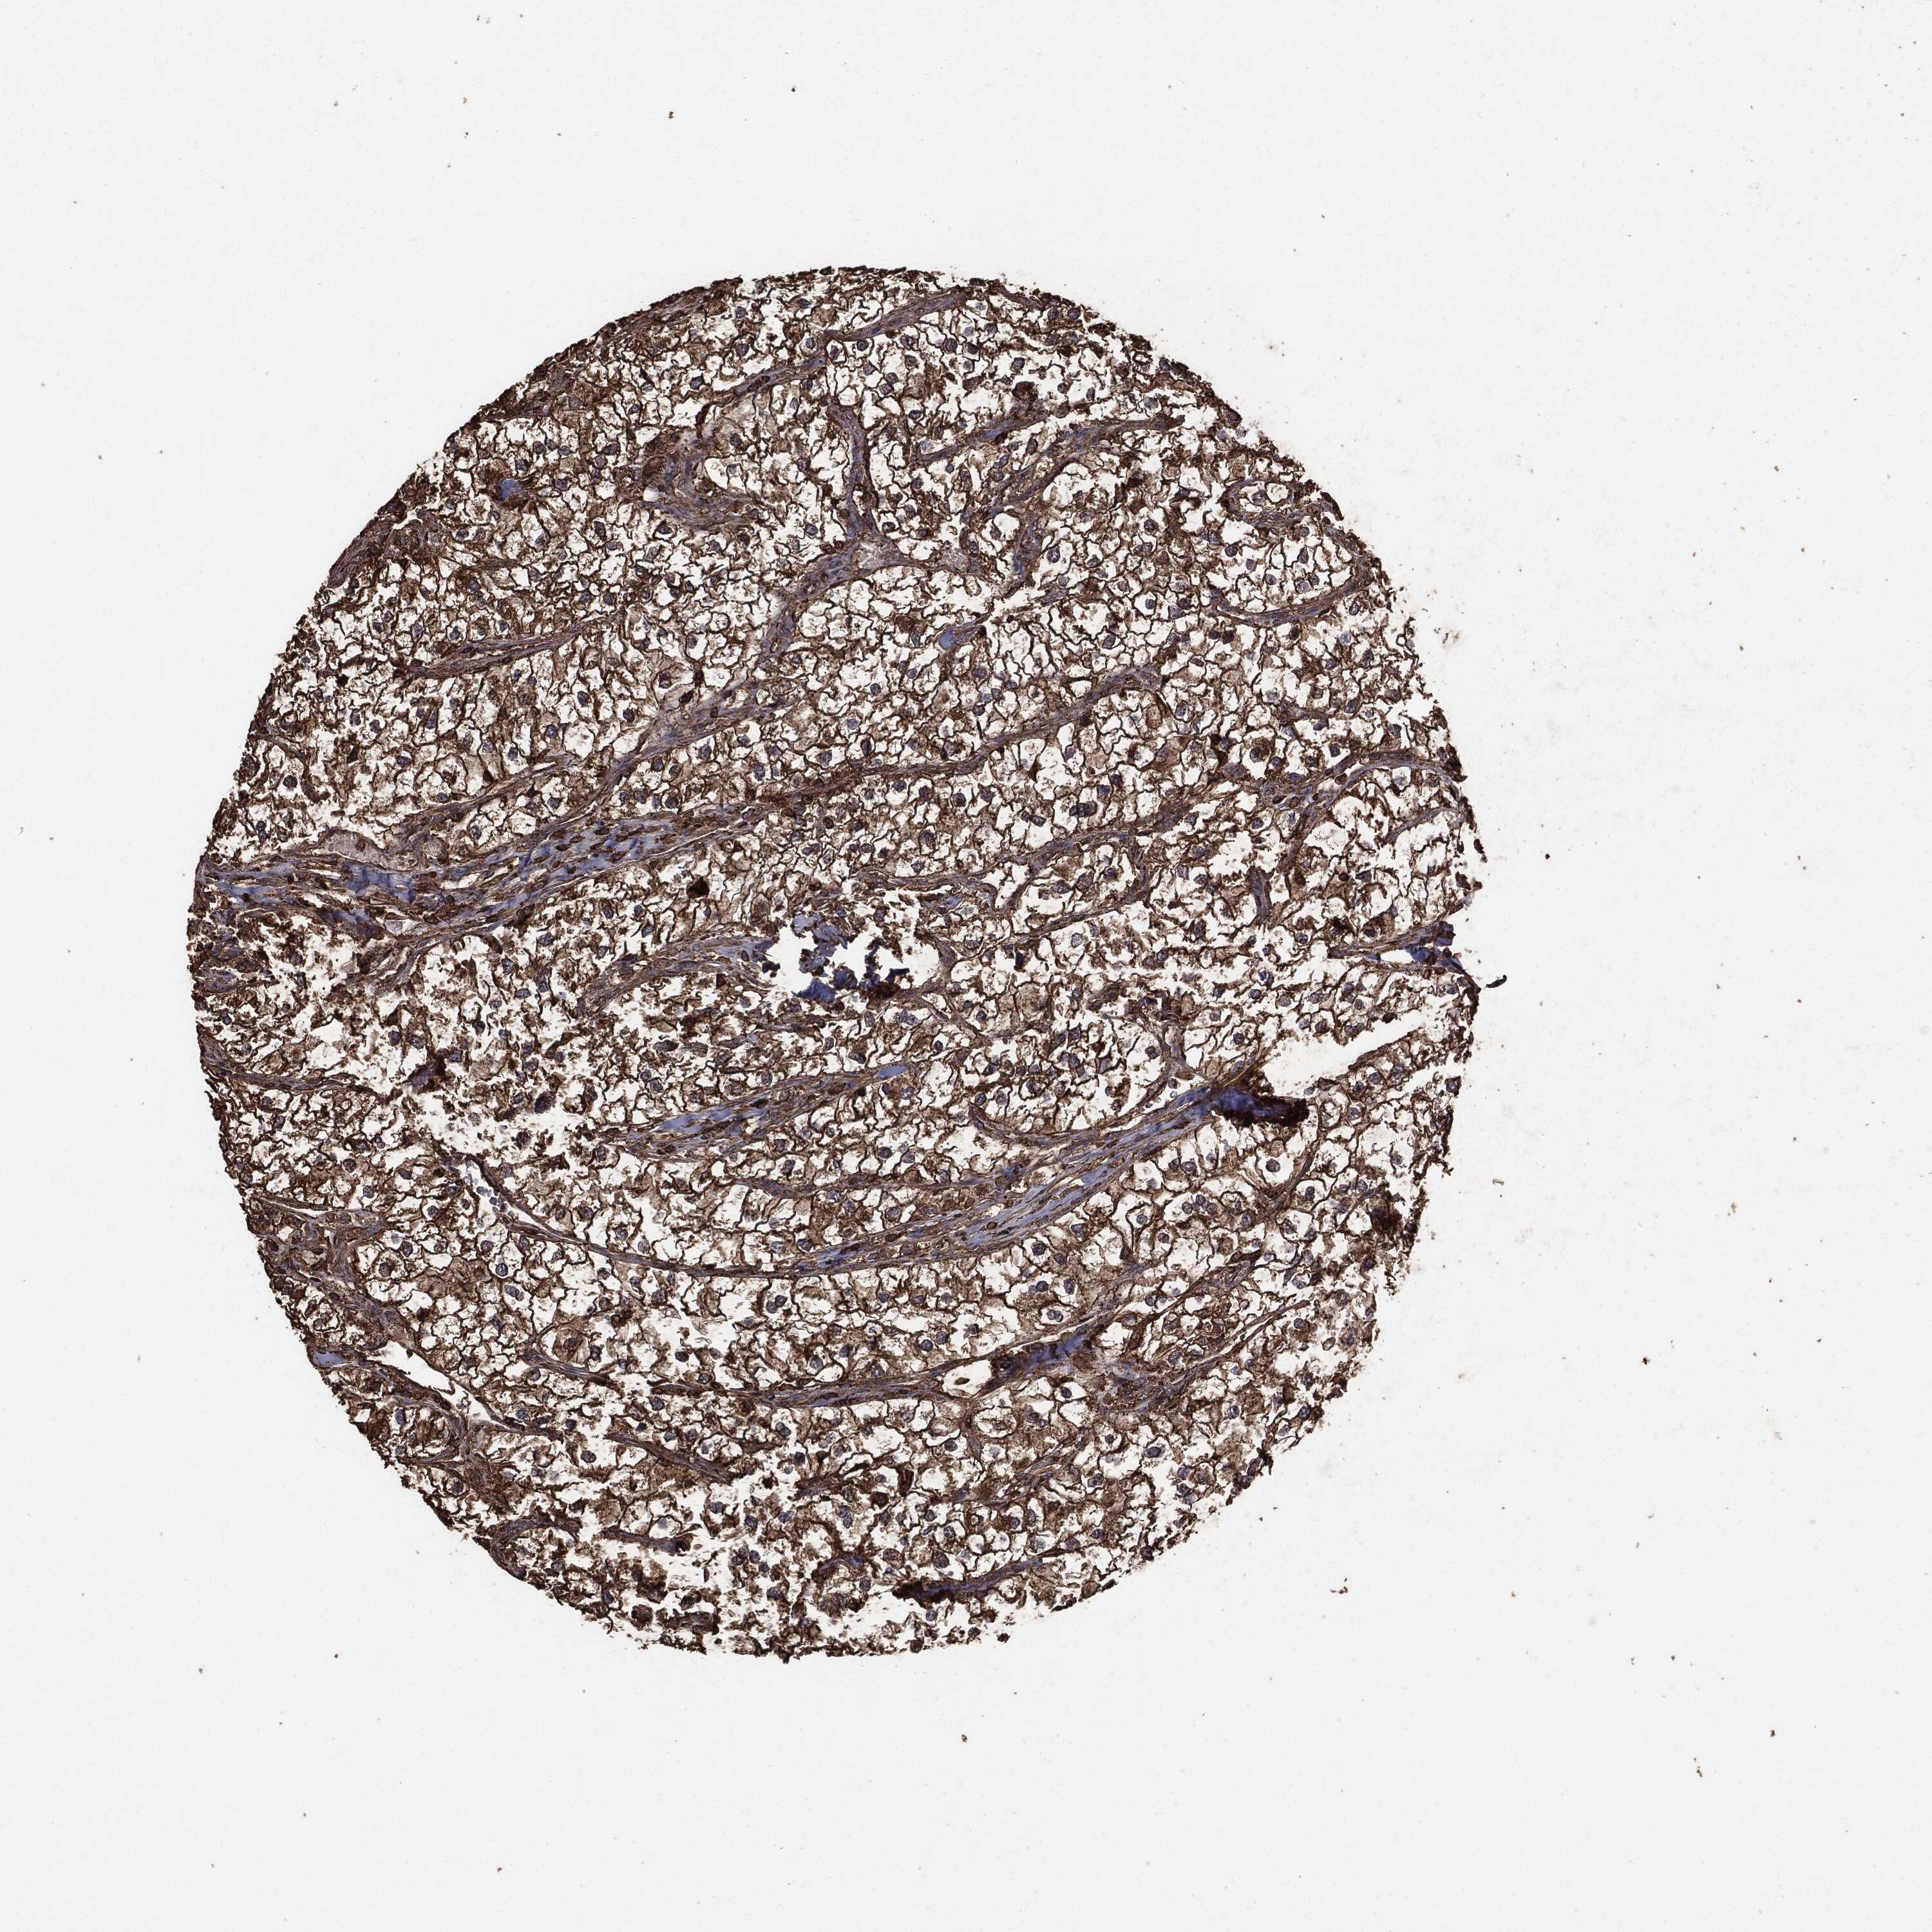

KIDNEY RENAL CLEAR CELL CARCINOMA (TCGA) - Interactive survival scatter ploti

The Survival Scatter plot shows the clinical status (i.e. dead or alive) for all individuals in the patient cohort, based on the same data that underlies the corresponding Kaplan-Meier plots. Patients that are alive at last time for follow-up are shown in blue and patients who have died during the study are shown in red.

The x-axis shows the expression levels (FPKM) of the investigated gene in the tumor tissue at the time of diagnosis. The y-axis shows the follow-up time after diagnosis (years). Both axes are complimented with kernel density curves demonstrating the data density over the axes. The top density plot shows the expression levels (FPKM) distribution among dead (red) and alive patients (blue). The right density plot shows the data density of the survived years of dead patients with high and low expression levels respectively, stratified using the cutoff indicated by the vertical dashed line through the Survival Scatter plot. This cutoff is automatically defined based on the FPKM cutoff that minimizes the p-score. The cutoff can be changed by dragging the vertical line or by entering a cutoff value in the square labeled "Current cut-off".

Under the Survival Scatter plot the p-score landscape (black curve; left axis) is shown together with dead median separation (red curve; right axis). Dead median separation is the difference in median mRNA expression between patients who have died with high and low expression, respectively. It is calculated as follows: median FPKM expression of dead patients with high expression - median FPKM expression of dead patients with low expression. This is intended to aid the user in visually exploring custom cutoffs and the associated p-scores and dead median separation.

Individual patient data is displayed and can be filtered by clicking on one or more of the category buttons on the top of the page. Categories describing expression level and patient information include: high, low, alive, dead, female, male and tumor stages. The scale of the x-axis can be toggled between linear and log-scale by clicking on the "x log" button. Mouse-over function shows TCGA ID, patient information and mRNA expression (FPKM) for each patient.

& Survival analysisi

Kaplan-Meier plots summarize results from analysis of correlation between mRNA expression level and patient survival. Patients were divided based on level of expression into one of the two groups "low" (under cut off) or "high" (over cut off). X-axis shows time for survival (years) and y-axis shows the probability of survival, where 1.0 corresponds to 100 percent.

MTOR is not prognostic in Kidney Renal Clear Cell Carcinoma (TCGA)

Best expression cut offi

Based on the FPKM value of each gene, patients were classified into two groups and association between prognosis (survival) and gene expression (FPKM) was examined. The best expression cut-off refers the FPKM value that yields maximal difference with regard to survival between the two groups at the lowest log-rank P-value. Best expression cut-off was selected based on survival analysis .

When clicking on this number, the vertical dashed line indicating cut-off, the interactive survival plot, and the Kaplan-Meier curve will be adjusted to show results based on the best expression cut-off.

: 12.09

P scorei

Log-rank P value for Kaplan-Meier plot showing results from analysis of correlation between mRNA expression level and patient survival.

N/A

5-year survival highi

5-year survival for patients with higher expression than the expression cutoff.

For melanoma and glioma, 3-year survival is shown.

5-year survival lowi

5-year survival for patients with lower expression than the expression cutoff.

TCGA RNA samplesi

RNA-seq data is reported as average FPKM (number Fragments Per Kilobase of exon per Million reads), generated by the The Cancer Genome Atlas (TCGA) .

Normal distribution across the dataset is visualized with box plots, shown as median and 25th and 75th percentiles. Points are displayed as outliers if they are above or below 1.5 times the interquartile range. FPKM values of the individual samples are presented next to the box plot.

Average pTPM 12.2

Number of samples 521